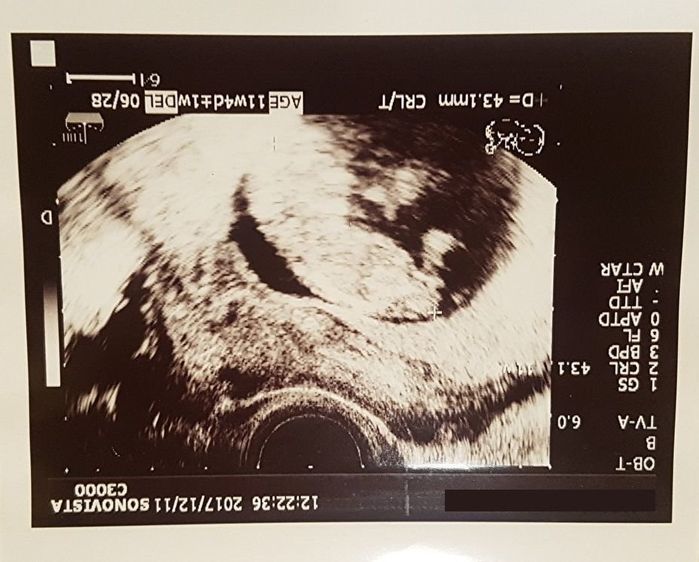

妊娠11週目 新天地で子どもの様子は?

1人で産んで育てることを決意し、彼から離れました。仕事のために転居し、初めての病院で健診を受けました。赤ちゃんの頭と体が形になってきた写真です。

CRL(頭殿長)43.1mmと、どんどん大きくなっていることを実感し、1人でも産む選択をした自分が誇らしく思えました。この頃からつわりがひどく、ファストフードのにおいを嗅ぐだけでも吐き気がしてしまうようになりました。